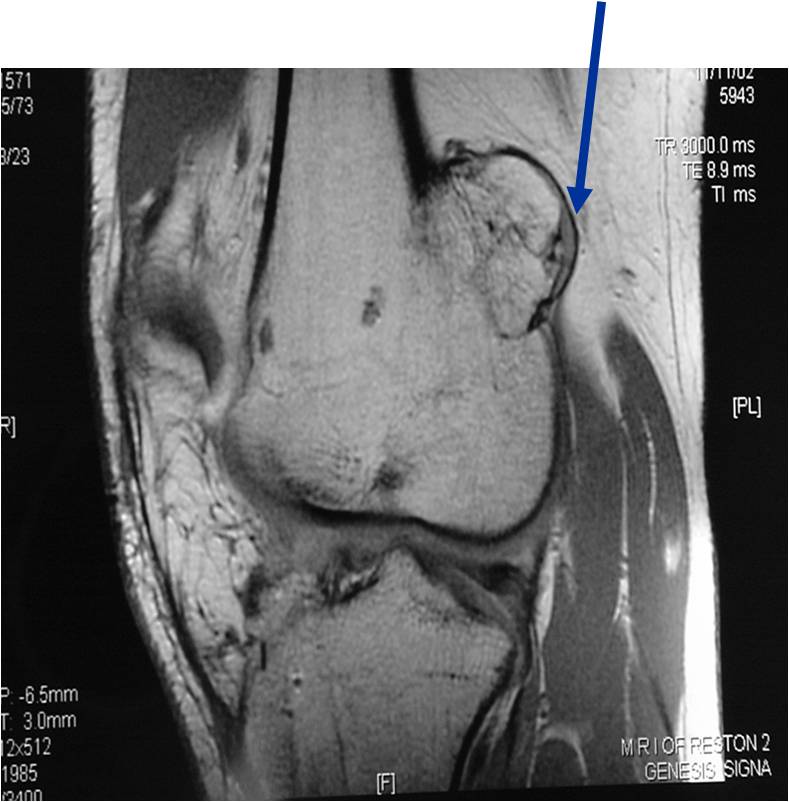

- Best test for evaluating thickness of cap and surrounding bursa

- Intermediate T1W Images

- High Intensity T2W Images because of fluid content

MRI: Secondary Chondrosarcoma of Proximal Femur: Thick Cartilage Cap (>2cm)